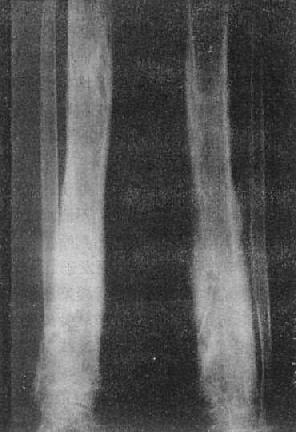

(二)骨质软化 骨质软化(osteomalacia)是指一定单位体积内骨组织有机成分正常,而矿物质含量减少。因此,1g骨内的钙盐含量降低。骨发生软化。组织学上显示骨样组织钙化不足,常见骨小梁中央部分钙化,而外面围以一层未钙化的骨样组织(图2-1-8)。

图2-1-8 前臂及小腿骨骨质软化—佝偻病骨质普遍密度减低,骨皮质薄,边缘不清,骨小梁

模糊,骨变弯、变形。干骺端宽大呈杯口状变形,骺与干骺干骺端距离增宽。骺边缘模糊。腕骨出现少

骨质软化的X线表现主要是由于骨内钙盐减少而引起的骨密度减低,以腰椎和骨盆为明显。与骨质疏松不同的是骨小梁和骨皮质边缘模糊,系因骨组织内含有大量未经钙化的骨样组织所致(图2-1-8)。由于骨质软化,承重骨骼常发生各种变形(图2-1-9)。此外,还可见假骨折线,表现为宽约1~2mm的光滑透明线,与骨皮质垂直,边缘稍致密,好发于耻骨支、肱骨、股骨上段和胫骨等。

在成骨过程中,骨样组织的钙盐沉积发生障碍,即可引起骨质软化。造成钙盐沉积不足的原因可以是维生素D缺乏,肠道吸收功能减退,肾排泄钙磷过多和碱性磷酸酶活动减低。骨质软化系全身性骨病,常见者发生于生长期为佝偻病,于成年为骨软化症。亦可见于其他代谢性和氟中毒骨疾患。